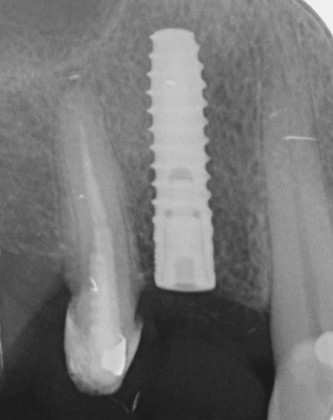

Röntgenkontrollaufnahme nach der Implantation. Das Implantat wurde inseriert wie geplant.